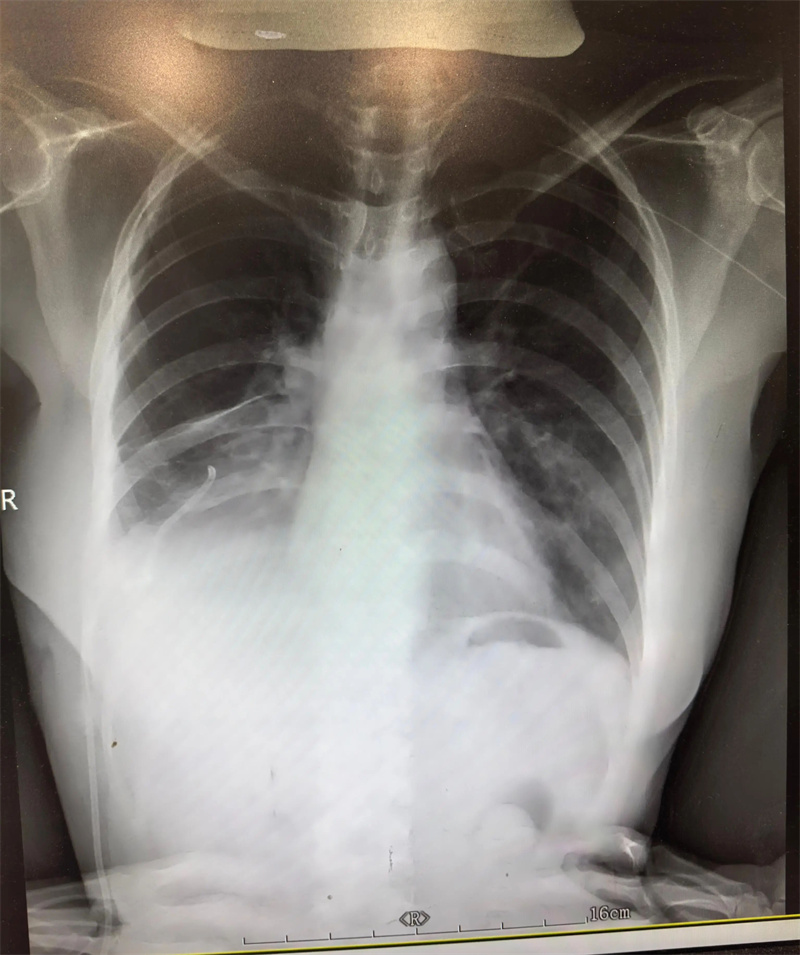

△图片非案例所提及